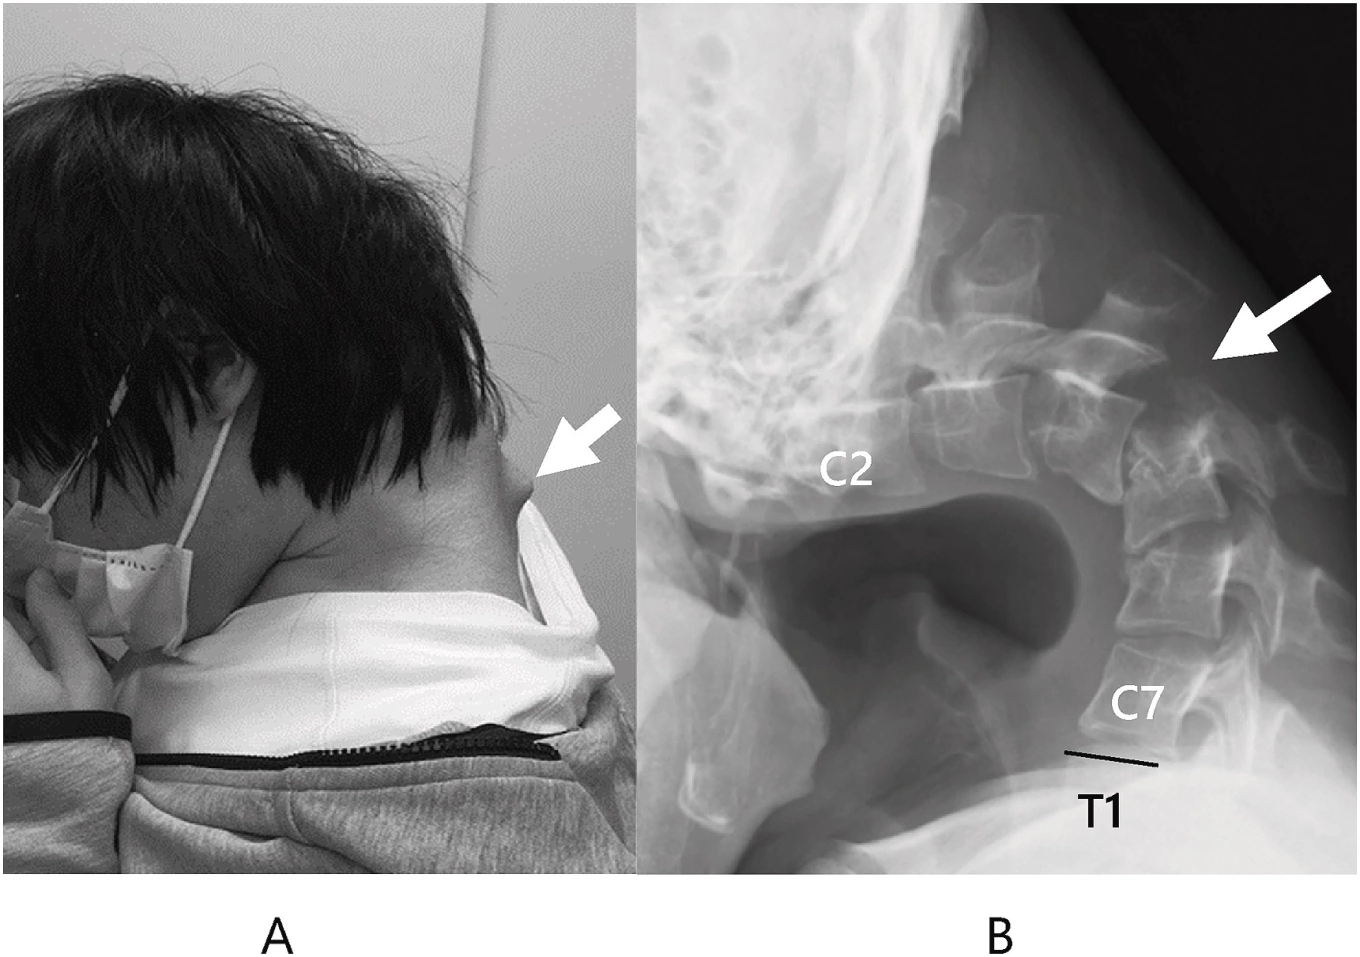

Diagnosis and Medical Evaluation

Diagnosing DHS typically involves a combination of: Neurological assessments, Muscle strength testing, Imaging studies (such as MRI or CT scans), Electromyography (EMG) to evaluate electrical activity in the muscles. Doctors aim to identify whether the cause is primarily muscular or neurological in origin. Ruling out structural issues like herniated discs or spinal injuries is also important during evaluation. In the case of the young man in Iran, medical imaging and clinical tests confirmed a fixed kyphotic posture (forward curvature of the upper spine) without signs of trauma. He also experienced persistent discomfort and sensations in his upper limbs, indicating possible nerve involvement.